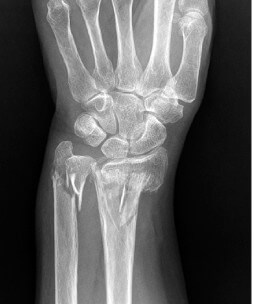

골다공증이란 뼈에서 무기질이 빠져나가 뼈의 밀도가 감소하고 이로 인해 이차적으로 병적 골절을 일으킬 수 있는 대사성 질환으로 주로 흉추(등뼈)와 요추(허리뼈)의 압박골절, 대퇴골 경부와 전자 간 부위 골절, 요골 하단(손목 부위) 골절등을 일으키게 됩니다.

골다공증 진단을 위해, 혈액을 통한 기본 검사인 칼슘과 인, 비타민 D , 갑상선 기능검사, 단백질등의 수치를 검사합니다. 단순 X-ray 촬영과 골밀도(BMD) 검사를 통해 골의 소실 정도를 알 수 있으며 필요시 MRI와 초음파 검사를 하기도 합니다.

골밀도가 -1에서 -2.5이면 골량 감소, -2.5 이하이면 골다공증으로 진단하며, 골밀도가 -2.5 이하면서 신체의 한 부위 이상에 병리적 골절이 있으면 중증 골다공증으로 분류합니다.